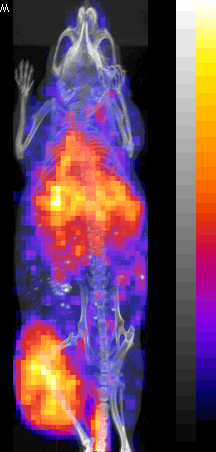

Nude mouse with a SUM190 tumor received intravenous antisense (anti-RIa)

18F-MORF/tat/Herceptin nanoparticle and PET/CT images obtained at at 3 and 8 hr.

111In labeled oligomer |